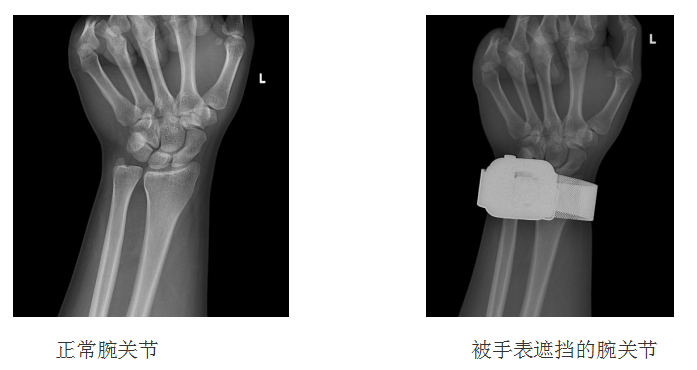

左侧正常的腕关节X光可以清晰地看见腕关节部分的皮肤,其内骨骼的轮廓,间隙等等细节,再看右侧被手表遮挡的腕关节,因为手表属于异物,X线穿过它也进行了衰减,形成了“戴了手表”的影像,手表部分的骨骼与其他组织完全被遮挡,无法进行诊断。